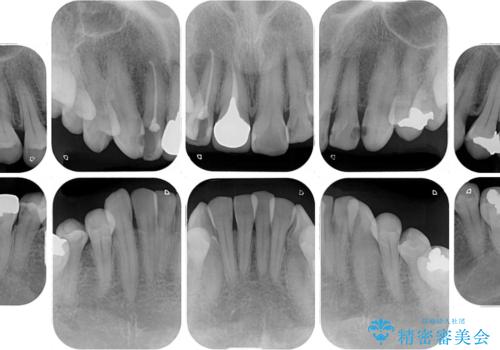

- 前歯の歯並びやむし歯治療の跡、奥歯の銀歯を気にして来院された患者様です。

インビザラインによる矯正治療の後に虫歯や銀歯をセラミックにて補綴することとしました。